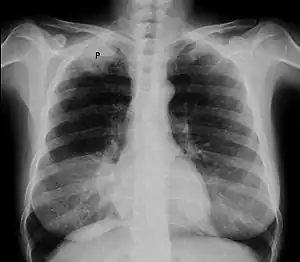

| Chest radiograph showing a Pancoast tumor (labeled as P, non-small cell lung carcinoma, right lung), from a 47-year-old female smoker. | |

Diagnosis of Pancoast tumor is usually made after evaluating clinical symptoms and imaging. Chest X-ray is a good screening test even though Chest CT scan can provide a better resolution and extent to which internal organs are being compressed.